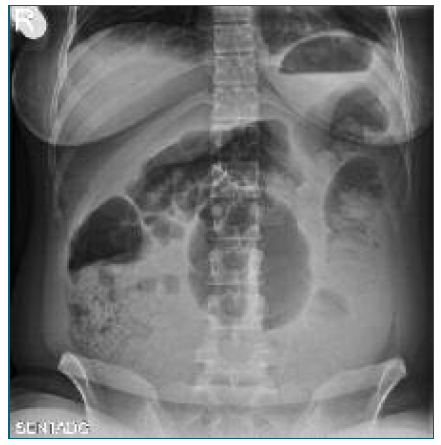

Initial laboratory tests revealed a hemoglobin drop from 11 g/dL in late pregnancy to 9.3 g/dL, suggesting mild postpartum anemia. A renal-bladder ultrasound and an abdominal X-ray imaging (Figure 1) were performed, excluding urinary and intestinal complications. Persistent pain along with an episode of lipothymia prompted an urgent abdominopelvic contrast-enhanced CT-scan, revealing a 19 cm retroperitoneal hematoma in the left flank and iliac fossa (Figure 2). Additionally, a 7 mm pseudoaneurysm in the LOA was identified as the source of intermittent hemorrhage (Figure 3A).

Figure 1 Abdominal X-ray performed due to suspected intestinal obstruction, revealing displaced and distended intestinal loops with obscuration of the psoas muscle contour. These findings are nonspecific and have low sensitivity for detecting retroperitoneal hemorrhage, notably in low- to moderate-volume hematomas.